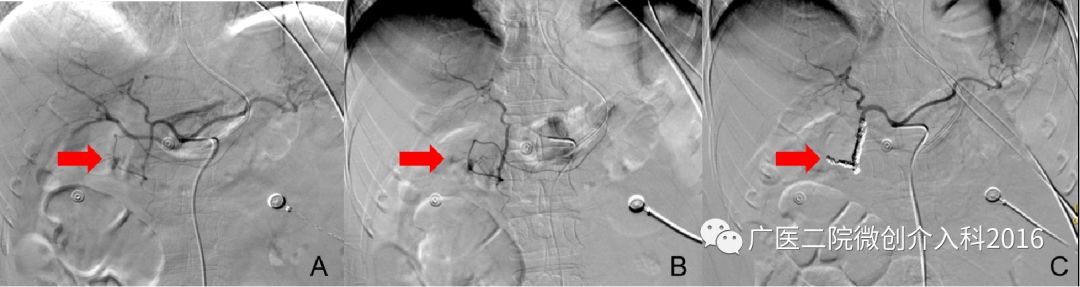

患者为十二指肠溃疡并大出血,经内科药物治疗效果不佳,仍有大量出血,生命垂危。图A、B行十二指肠动脉造影,可见造影剂浓聚和外渗,精准找到出血部位和责任血管。通过注入弹簧圈堵塞出血血管,图C再次造影可见原出血征象消失,患者出血停止。经后续治疗,患者脱离生命危险。